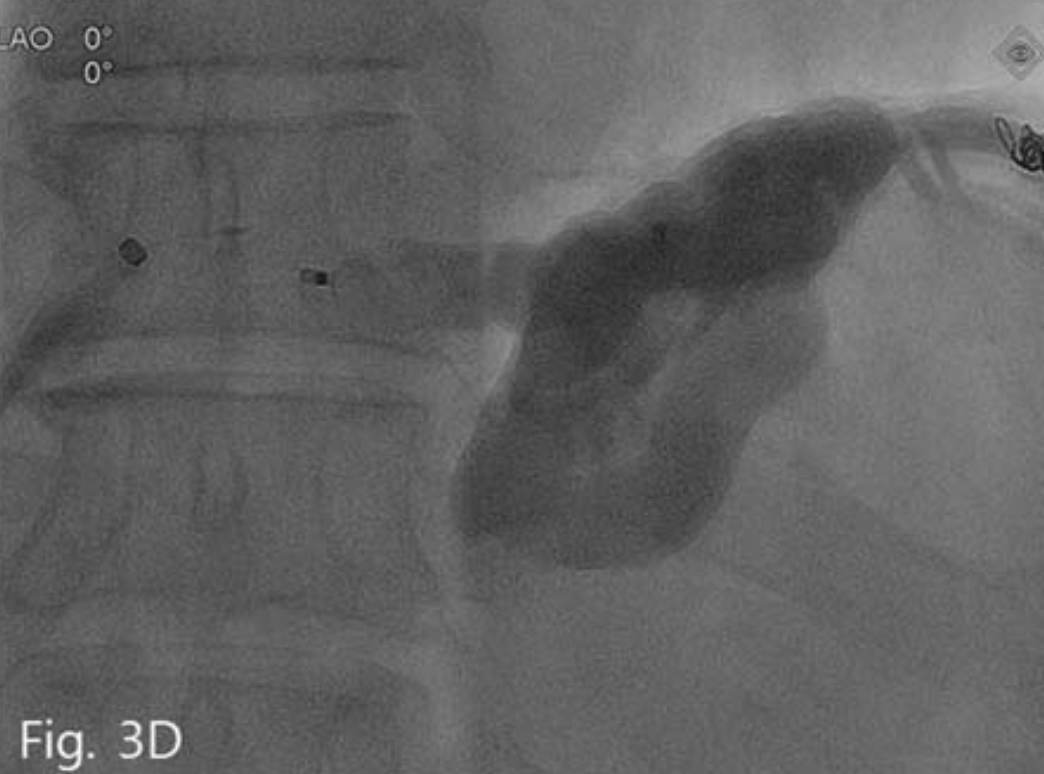

Upjohn, Kalamazoo, Mich)로 위정맥류내를 충분히 채우고 일부는 유입정맥까지 역류시킨 후 plug를 분리하고 시술을 마쳤다(Fig. 3D).

D. Vascular plug is success fully detached.